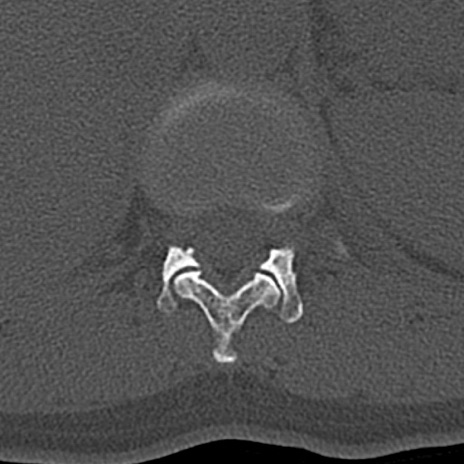

【整形】TIPS症例4 腰椎CT(横断像)

腰椎CT

横断像と矢状断像